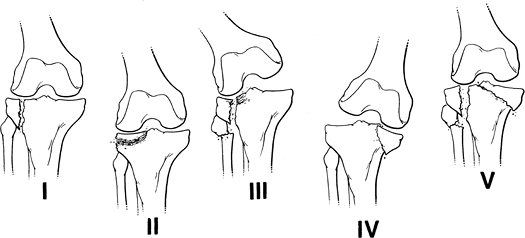

Skeletal Trauma: Proximal Tibial Fractures

Key Facts

Proximal tibial fractures may be extra-articular or articular (tibial plateau or condylar fractures).

Tibial plateau (condyle) fractures

account for 1% of all fractures and 8% of fractures in the elderly. The

majority (55%–70%) of plateau fractures involve the lateral plateau.

Isolated medial plateau factures occur in 10% to 23% of cases, and

medial and lateral fractures occur in 10% to 30% of cases. -

![]() |

FIGURE 5-8

Hohl classification of tibial plateau fractures: I, undisplaced fracture (24%); II, central depression (26%); III, split compression, usually with fibular fracture (29%); IV, total condylar depression (11%); V, comminuted bicondylar fractures (10%). |